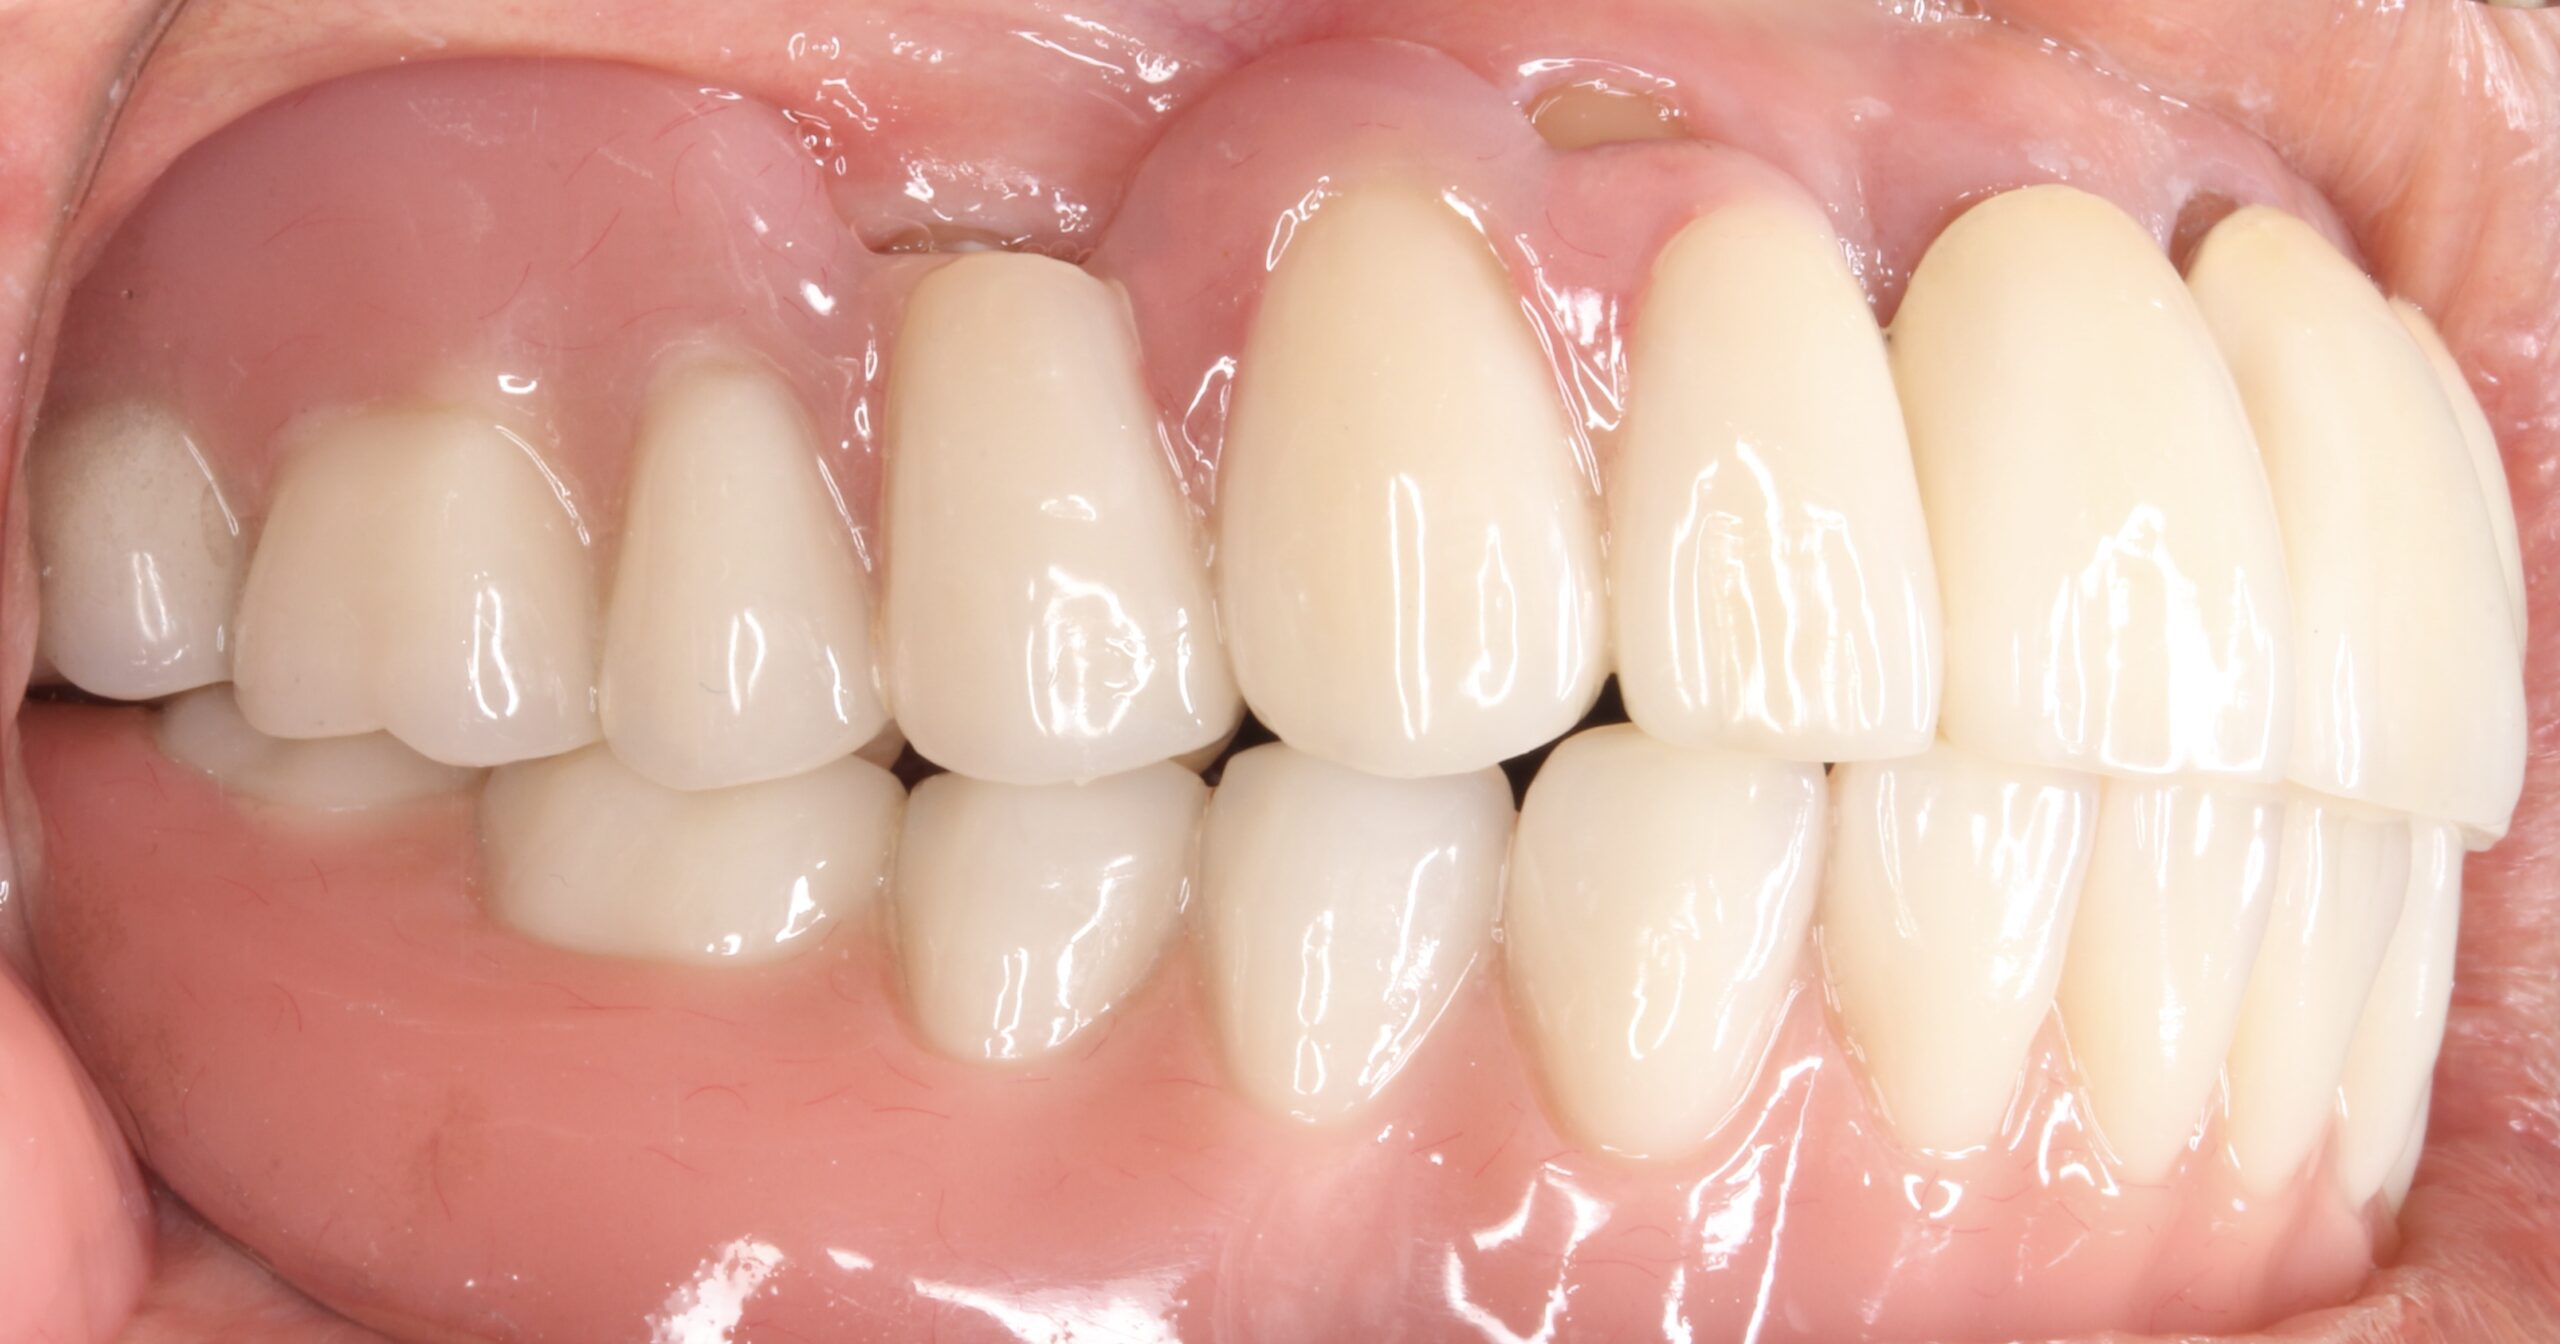

上顎はコーヌステレスコープ、下顎はレジリエンツテレスコープにて治療を行なった。

【治療後】